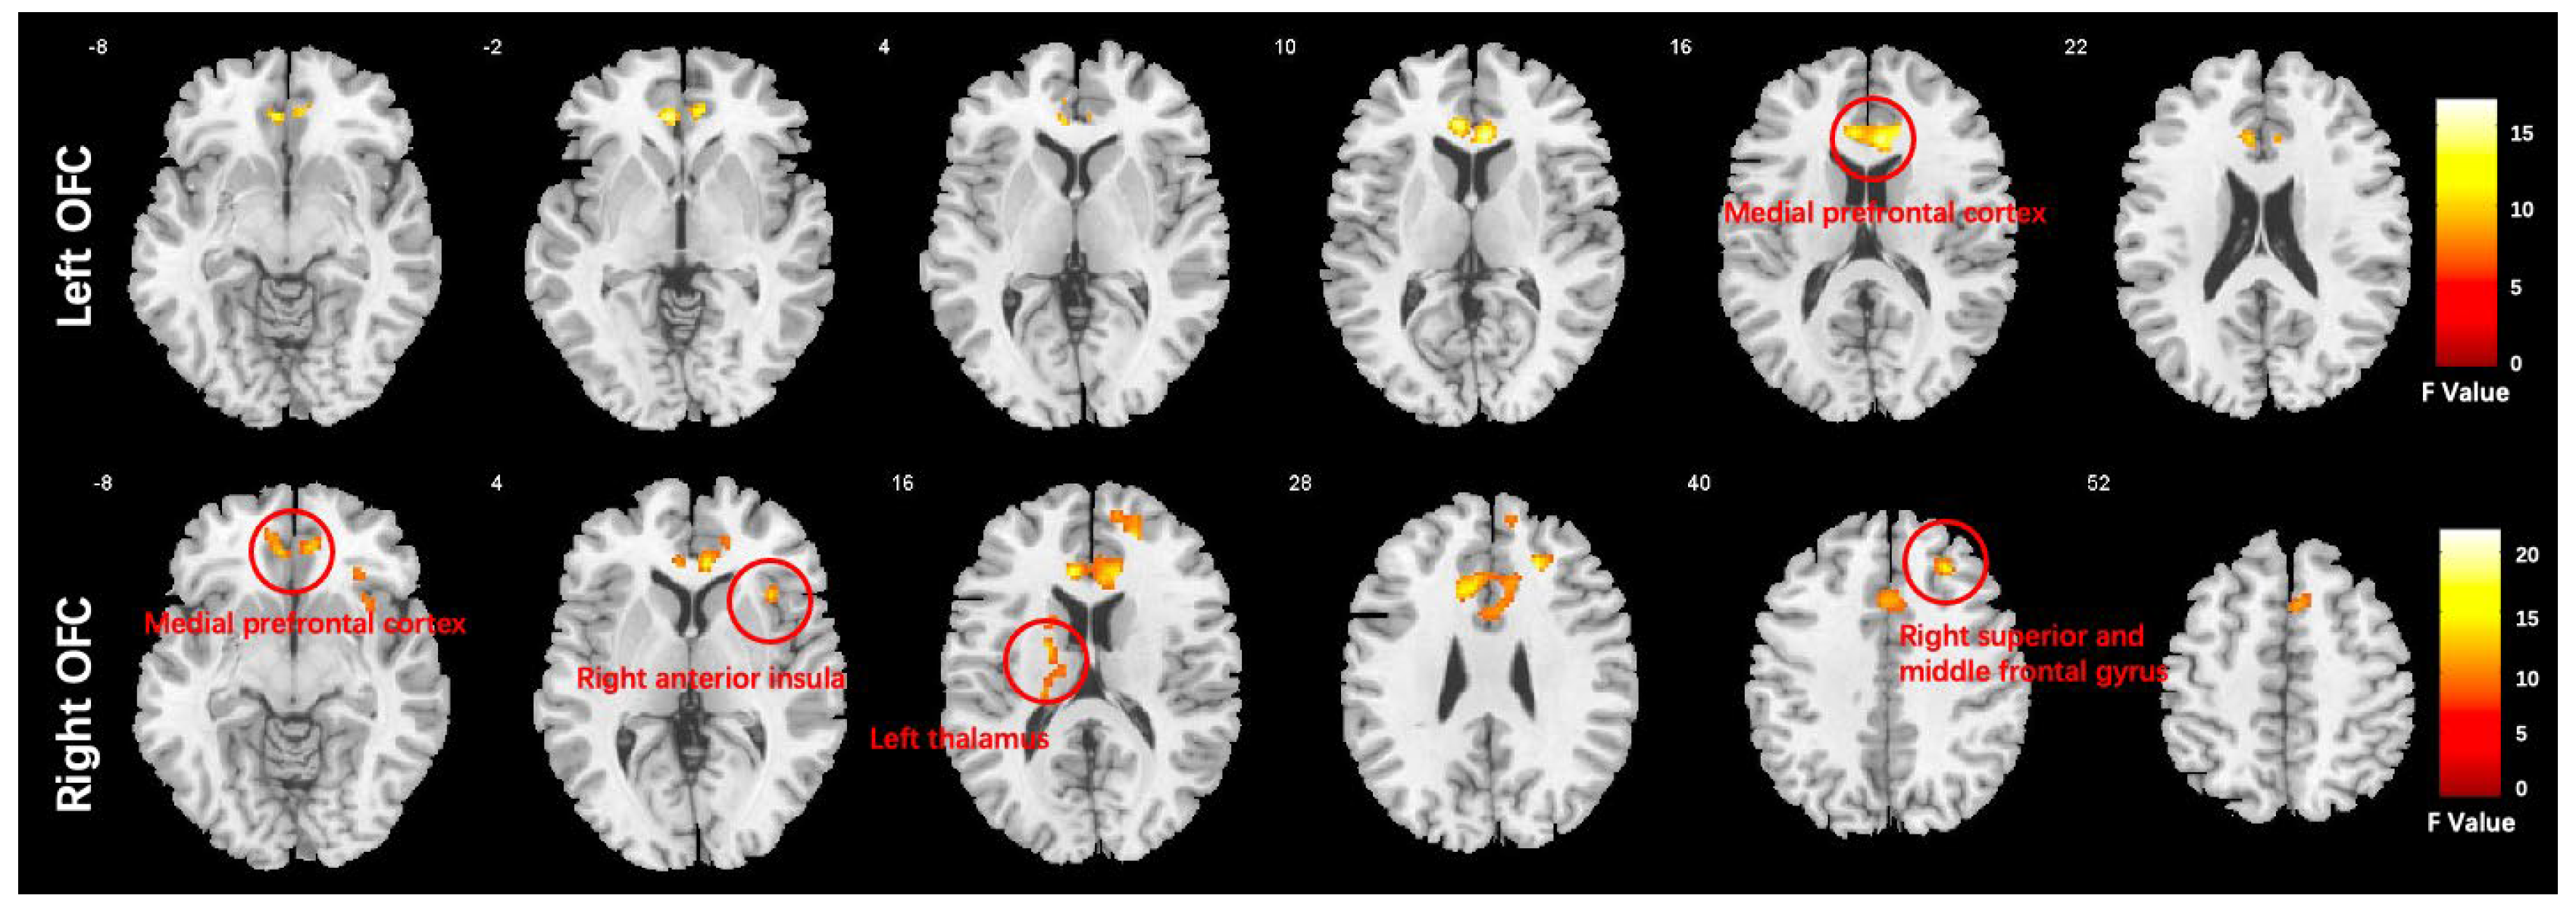

| Seed: left orbitofrontal cortex | |||||||

| Medial prefrontal cortex | 6, 32, 12 | 0.303 ± 0.113 | 0.273 ± 0.085 | 0.121 ± 0.117 | 15.95 | <0.001 | 501 |

| Seed: right orbitofrontal cortex | |||||||

| Medial prefrontal cortex | 8, 32, 10 | 0.246 ± 0.086 | 0.263 ± 0.087 | 0.090 ± 0.88 | 20.04 | <0.001 | 1542 |

| Right anterior insula | 34, 14, −14 | 0.234 ± 0.100 | 0.230 ± 0.111 | 0.071 ± 0.115 | 14.92 | <0.001 | 236 |

| Right middle frontal gyrus | 22, 34, 30 | 0.119 ± 0.112 | 0.128 ± 0.100 | −0.023 ± 0.104 | 17.95 | <0.001 | 181 |

| Left thalamus | −20, −24, 20 | −0.063 ± 0.126 | 0.0193 ± 0.117 | 0.117 ± 0.095 | 13.43 | <0.001 | 126 |